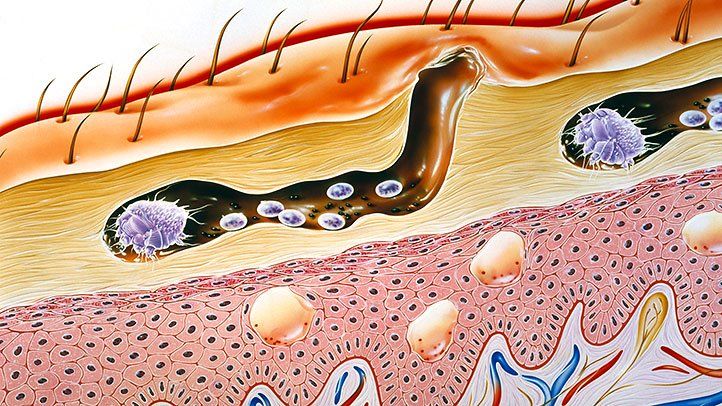

SCABİES (UYUZ)

Uyuz; Sarcoptes scabiei var. Hominis adı verilen akarın (böcek) sebep olduğu tüm dünyada yaygın olarak görülen bir hastalıktır.

Uyuz böceği deride tüneller açarak bu tünellerin içinde yaşar.

İlk defa uyuza yakalanan bir kişide belirtilerin başlaması 2-6 hafta kadar sürebilir. Ancak daha önce uyuza yakalanan bir kişide, belirtiler genellikle maruz kaldıktan 1-4 gün içinde ortaya çıkar. Hastalık belirtilerinin başlamadığı bu dönemlerde bile kişi uyuzu başkalarına bulaştırabilir.

Uyuzun en önemli belirtisi şiddetli gece kaşıntısıdır. Kaşıntı, kişinin yatağa girip ısınması ile artar ve kişiyi uykudan uyandırabilecek şiddette iken gündüzleri daha hafiftir. Kaşıntı genellikle el parmak araları, el bileğinin iç yüzü, bilekler, koltuk altları, dirsekler ve kasıklarda görülmekle birlikte tüm vücutta görülebilmektedir. Hastalığın en belirgin bulgusu parmaklar arasında dalgalı kirli bir çizgi halinde görülen, uyuz böceğinin içinde yaşadığı, gri beyaz renkli, 1-10 mm uzunluğundaki tünellerdir. Kişilerde özellikle geceleri artan şiddetli kaşıntı ve deride görülen içi su dolu keseciklerin görülmesi uyuz şüphesini arttırır.

Uyuz; Sarcoptes scabiei var. Hominis adı verilen akarın (böcek) sebep olduğu tüm dünyada yaygın olarak görülen bir hastalıktır.

Uyuz böceği deride tüneller açarak bu tünellerin içinde yaşar.

İlk defa uyuza yakalanan bir kişide belirtilerin başlaması 2-6 hafta kadar sürebilir. Ancak daha önce uyuza yakalanan bir kişide, belirtiler genellikle maruz kaldıktan 1-4 gün içinde ortaya çıkar. Hastalık belirtilerinin başlamadığı bu dönemlerde bile kişi uyuzu başkalarına bulaştırabilir.Uyuzun en önemli belirtisi şiddetli gece kaşıntısıdır. Kaşıntı, kişinin yatağa girip ısınması ile artar ve kişiyi uykudan uyandırabilecek şiddette iken gündüzleri daha hafiftir. Kaşıntı genellikle el parmak araları, el bileğinin iç yüzü, bilekler, koltuk altları, dirsekler ve kasıklarda görülmekle birlikte tüm vücutta görülebilmektedir. Hastalığın en belirgin bulgusu parmaklar arasında dalgalı kirli bir çizgi halinde görülen, uyuz böceğinin içinde yaşadığı, gri beyaz renkli, 1-10 mm uzunluğundaki tünellerdir. Kişilerde özellikle geceleri artan şiddetli kaşıntı ve deride görülen içi su dolu keseciklerin görülmesi uyuz şüphesini arttırır.